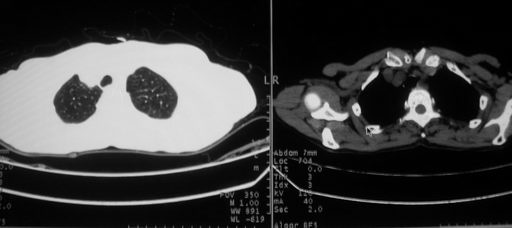

以下是引用zjzjr在2008-5-19 13:40:00的发言:[br]支持左上肺周围型肺癌(腺癌可能性大)伴颅内多发性转移.